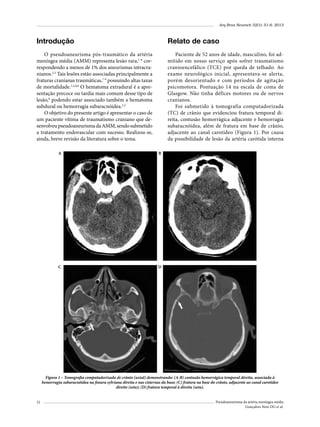

Figura 1 (A-B) – Imagens de RM ilustrando os cortes utilizados no plano axial e coronal para localizar o “ponto".

Figura 2 – Corte coronal na topografia da cabeça do hipocampo,

ilustrando a mensuração do corredor cirúrgico. (A): ponto lateral

basal; (B): ponto medial superior; (C): ponto medial inferior;

D: ponto basal.

A distância média (a) canal auditivo-ponto hipocampal foi de 31,9 mm [mínimo (c) 24,7 – máximo (b)

39,6 mm] (Figura 3 A-B).

Neste estudo, identificou-se esse ponto craniométrico (ponto hipocampal), localizado em média a 31,9

mm do canal auditivo externo (Figura 3A e B).